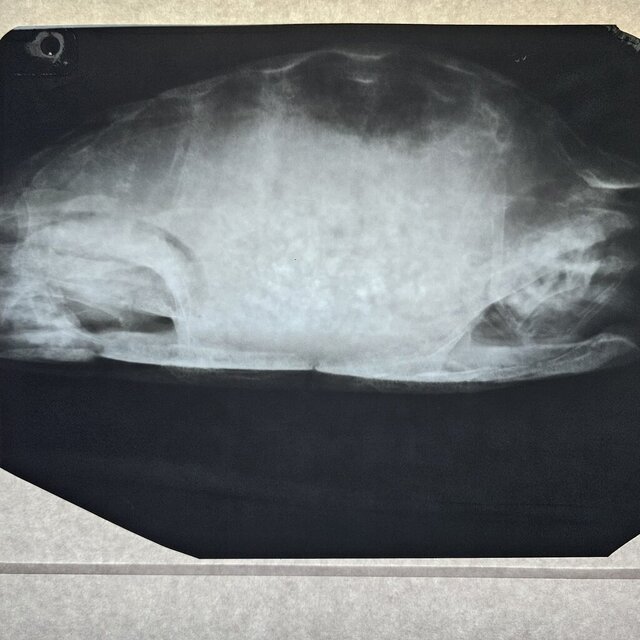

Добрый день. Сходили в клинику Степаненко в Харькове, но приём вела не она. Сдали кровь её удалось взять очень мало. Сделали ренген. Получили назначения. Там нам вкололи Элеовит. Сказали что все очень плохо. Анализ крови скину завтра клиника не прислала

Назначения из клиники